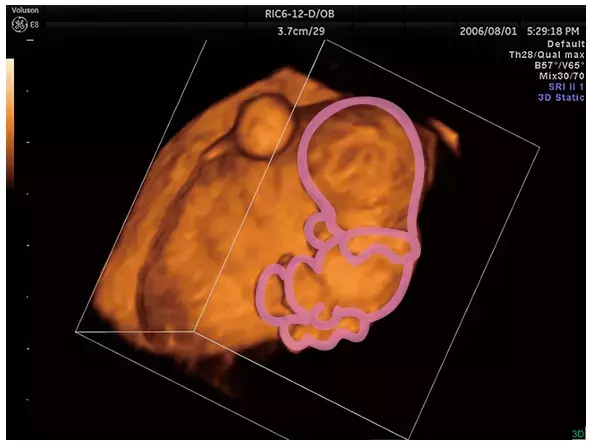

妊娠3ヶ月のエコー(超音波)写真

3Dは詳細に、小さな手と足、顔と胴体の区別がつき、赤ちゃんの様子がリアルに分かります。

手足だけでなく関節の位置まで分かる3D写真。胎盤も確認できます。

写真提供:東京マザーズクリニック